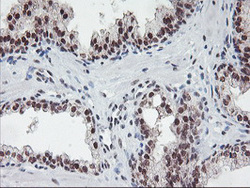

Immunohistochemistry

LS-C785746 IHC